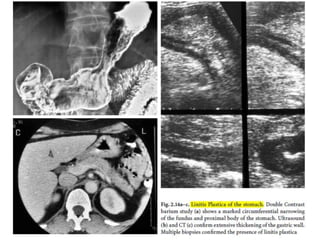

Crohn’s Disease of the stomach.

Double Contrast barium study (a) shows distortion of the normal

gastric mucosal pattern with marked nodularity and multiple

aphthous lesions. Note the irregular scalloping affecting the greater

curve, due to active Crohn’s Disease.

Ultrasound (b) and Endoscopic-ultrasound (c) show marked transmural

thickening of the gastric wall. The muscularis propria is intact